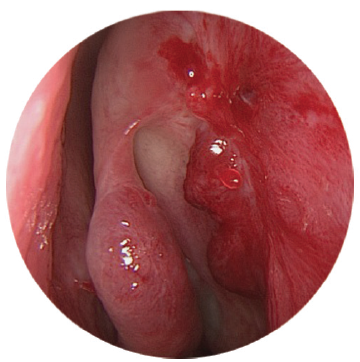

The study included patients with complaints of long-term lacrimation and suppuration (more than 6 months). The patients were diagnosed and treated at various institutions – at otorhinolaryngological and ophthalmological departments of the Pirogov State clinical hospital (Moscow) and hospitals of the MEDSI group of companies (Moscow) with the established diagnosis of “chronic dacryocystitis” during the period from 2015 to 2019. The clinical examination of patients included disease history, biomicroscopy of the anterior segment with evaluation of the eyelids, and anterior rhinoscopy. Endoscopic examination of the nasal cavity was performed using rigid endoscopes of 0° and 30° and 4 mm in diameter, after local application anesthesia with 10% lidocaine hydrochloride solution, with examination of all the endonasal structures of the nasal cavity: inferior nasal meatus, nasal floor, inferior nasal concha, middle nasal meatus, osteomeatal complex, area of the hamate bone, front end of the middle turbinate, and lacrimal tubercle of the nasal septum (Fig. 1–3).

Fig. 2. Endoscopy of the nasal cavity. Endoscope 4 mm 0°. The enlarged concha bullosa obstructs access to the operating field